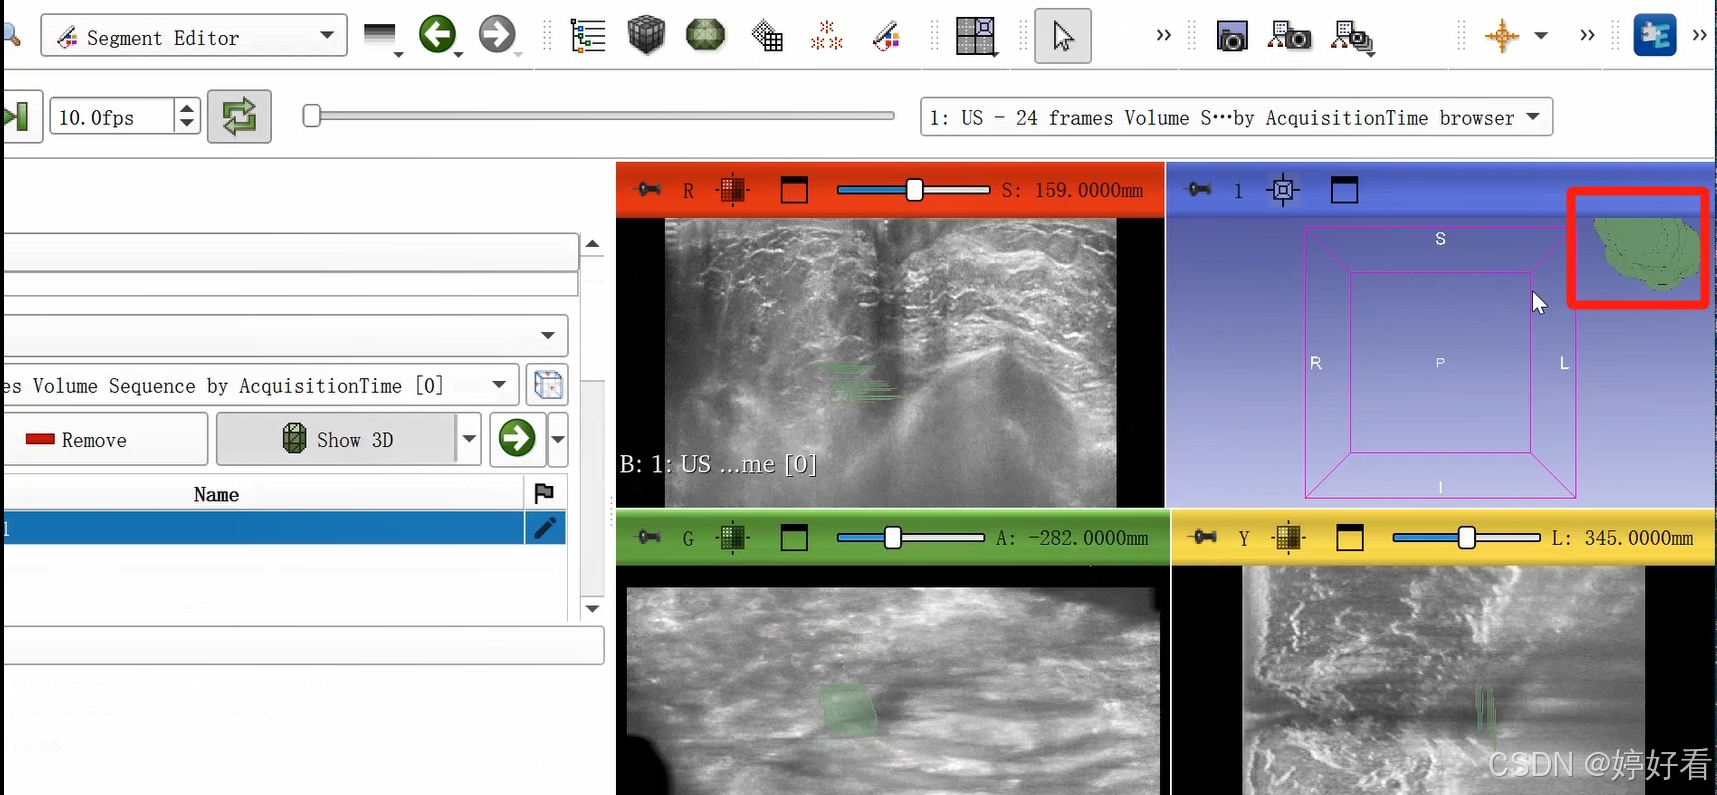

这是一个三维的图像,我们只要在一个面上勾画就可以了,另外两个面会自动显示勾画的区域。

2.4 点击Show 3D,显示三维图像。